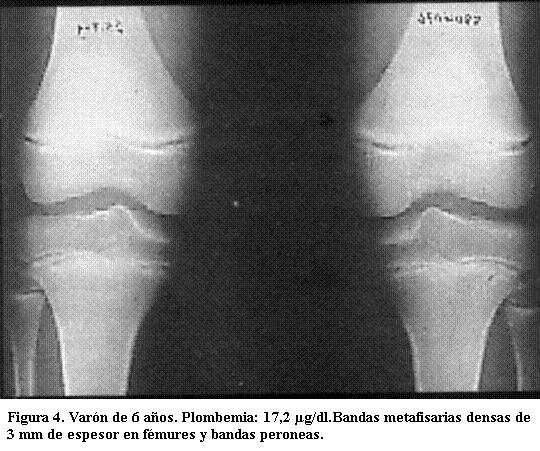

Predominan en las de crecimiento más rápido (las ubicadas en rodillas y muñecas) incluido el peroné, signo de importancia ya que otras enfermedades que producen bandas densas metafisarias no afectan este hueso (3).

Tienen varios milímetros de espesor y sus límites son nítidos. Son tanto más densas cuanto mayor sea el grado de absorción del metal y tanto más anchas cuanto más haya durado el proceso de absorción (figuras 3, 4 y 5) (5).